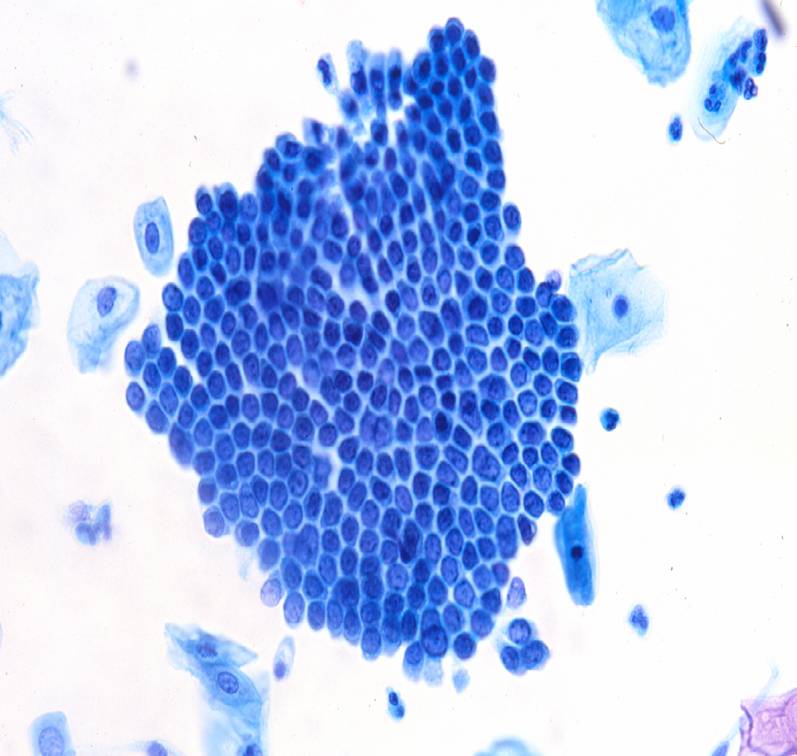

TBS-26.颈管内膜细胞

TBS-27.颈管内膜细胞

TBS-28.颈管内膜细胞